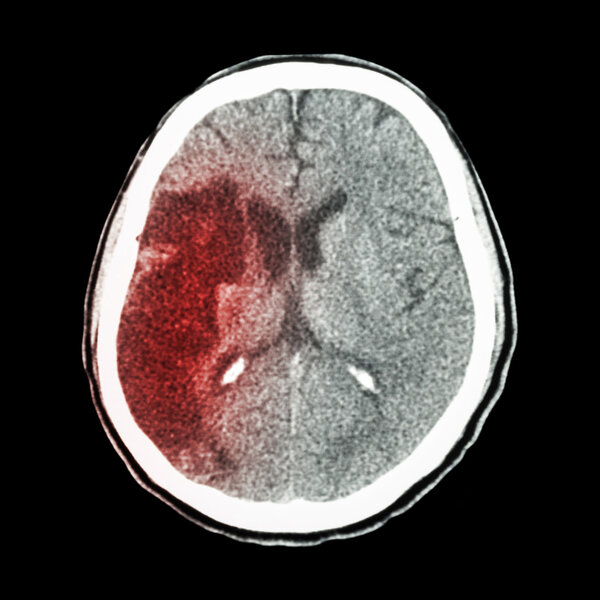

为将《健康加油站》打造成市民喜爱的精品节目,北京城市广播与市医院管理局及21家市属医院精心策划,根据季节特点、各疾病日和各医院学科特色安排了2014全年的节目选题,一年四季各类易发多发疾病的预防、节假日养生保健等应有尽有,并分专业从疾病识别、预防保健、治疗手段、如何做好病患家属等角度进行专题系列策划,同一领域专家讲解各有专长,使听众对一类疾病有全方位的了解,形成系统系列科学的健康大餐。比如,正值冬季,天气寒冷,心脑血管疾病易发多发,《健康加油站》在元旦首播头两周,精心推出了《健康 “从心开始”》、《防治卒中面面观》两个系列专题。安贞医院五位专家名医将在元旦1日至5日,轮流为大家送上心脏健康知识、消除疾病误区。宣武医院的7位专家将在元月的6日至12日奉上“大脑健康路路通”等专题,介绍脑卒中的预防、治疗、康复和护理等。

2014年1月6日—1月12日 《防治卒中面面观》

1月6日 大脑健康路路通(脑卒中的内科防治)宣武医院神经内科副主任 武剑教授

1月7日 突发脑卒中的自救与他救宣武医院急诊科副主任 孙长怡教授

1月8日 防“卒”早知道(颈动脉超声的认知)宣武医院血管超声科主任 华扬教授

1月9日 治“卒”有妙计(脑血管病外科治疗)宣武医院副院长 吉训明教授

1月10日 防“卒”有新解(脑卒中的中西医防治) 宣武医院神经内科副主任 高利教授

1月11日 脑卒中康复知道少宣武医院康复科主任 宋为群教授

1月12日 脑卒中患者的家庭护理宣武医院神经内科护士长 王玲